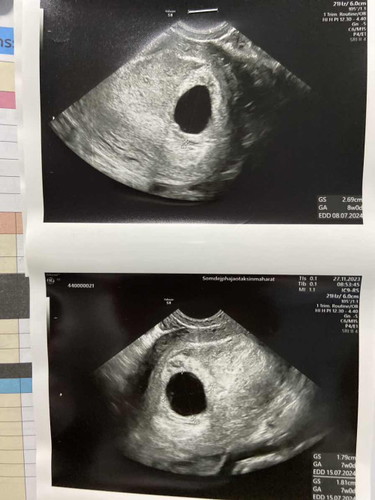

ท้อง 7 วีค ซาวไม่เจอตัวอ่อนเจอแต่ถุงตั้งครรภ์

คุณหมอให้โอกาสอีก2สัปดาห์ค่ะ ถ้าไม่เจอน้อง คุณหมอบอกว่าอาจจะท้องลมได้ เครียดมากเลยค่ะ 🥺

คุณหมอให้เวลาอีก2wเหมือนกันค่ะไปซาวมาวันนี้8+1w ไม่เจอเหมือนกันค่ะว่าจะไม่เครียดแต่อดไม่ได้เลยจริงๆ